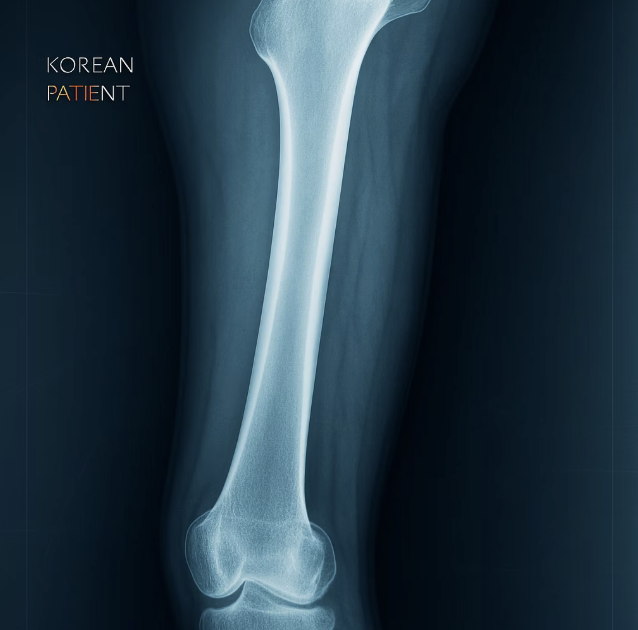

드물지만 알아둬야 할, 비전형 대퇴골 골절

매우 드물지만, 골다공증 주사를 아주 오랫동안(보통 5년 이상) 맞은 일부 환자에게서 ‘비전형 대퇴골 골절’이 보고되기도 합니다. 이는 넘어지거나 다치지 않았는데도 허벅지 뼈(대퇴골)의 특정 부위에 금이 가거나 부러지는 현상입니다. 뼈를 강하게 만드는 약이 오히려 뼈에 무리를 주는 역설적인 상황처럼 보일 수 있습니다.

이 부작용의 중요한 전조 증상은 바로 골절이 발생하기 몇 주 혹은 몇 달 전부터 허벅지나 사타구니 부위에 뻐근하고 묵직한 통증이 나타난다는 점입니다. 만약 장기간 주사 치료를 받고 있는데 이러한 종류의 통증이 느껴진다면, 이를 단순한 근육통으로 여기지 말고 반드시 주치의와 상담해야 합니다. 미리 발견하면 더 큰 골절을 예방할 수 있습니다.